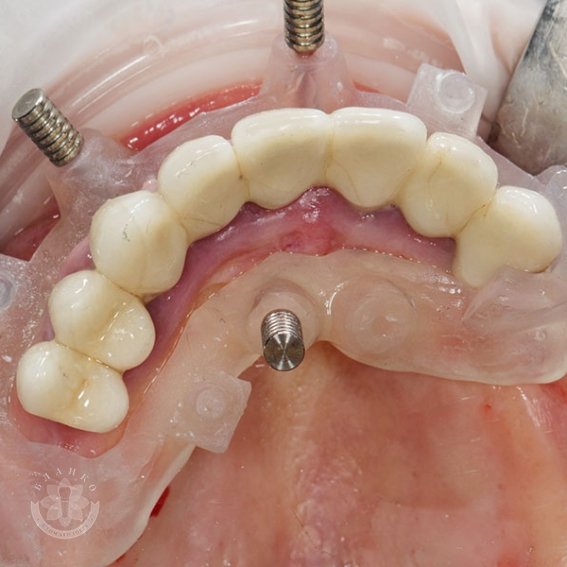

After successful implantation, a non-removable zirconium oxide structure is installed on the implants, which is characterized by high strength, aesthetics and durability.

Installation of six implants "turnkey" is a comprehensive dental service that includes all stages of treatment, from diagnostics to installation of a fixed structure. In the complete absence of teeth in the jaw (edentia),six implants are distributed in certain areas to evenly distribute the load.

The procedure usually consists of several stages: diagnostics, treatment planning, installation of implants and subsequent fixation of a fixed prosthesis.

After successful engraftment of the implants, a temporary structure is installed, and then the final zirconium work. In some cases, it is possible to speed up the process thanks to modern methods of immediate loading, but this depends on the condition of the bone tissue.